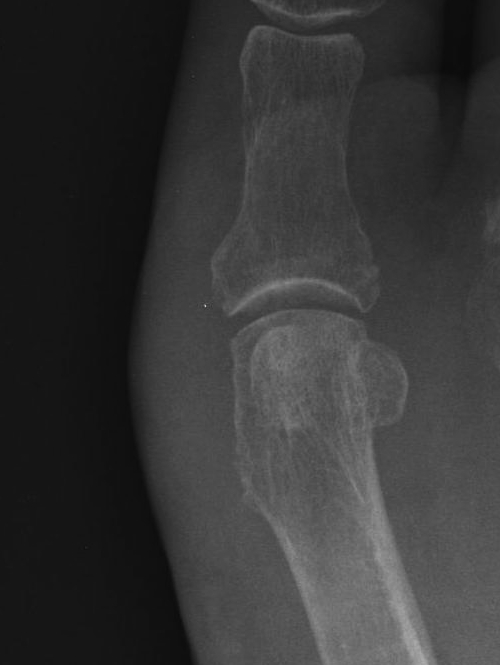

Hallux Varus

Cause

- excessive medial resection

- resection of lateral sesamoid

- excessive lateral release or medial plication

Issues

- difficulties with shoe wear

Options

- arthrodesis

- soft tissue reconstruction

EHL Reconstruction

- lateral two thirds of the tendon removed from its insertion

- detached distally, passed under transverse ligament

- inserted into proximal phalanx